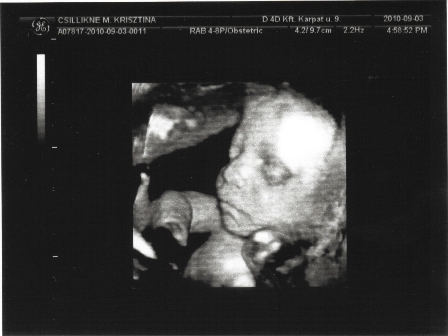

Kicsit eltűntem, nagy volt a fennforgás.... elkezdtük Bálinttal az iskolát, nagyon élvezi és már kapott három piros csillagot és piros pontot. Lukács oviban, így reggel mindig rohanás.... ráadásul összeszedtem valami nyavalyás vírust, így napok óta az ágyat nyomom :-( Voltam 4D-n, majd rakok föl képet... sajnos a lepény elkezdett meszesedni, GI szerint semmi gond egyelőre, de gyakrabban kell nézni, mert ha idő előtt eléri a III. fokozatot, akkor kórház...

Húúúú, várjuk a 4D-s képet. Amikor csináltattam én is felraktam. Olyan cukik :-)